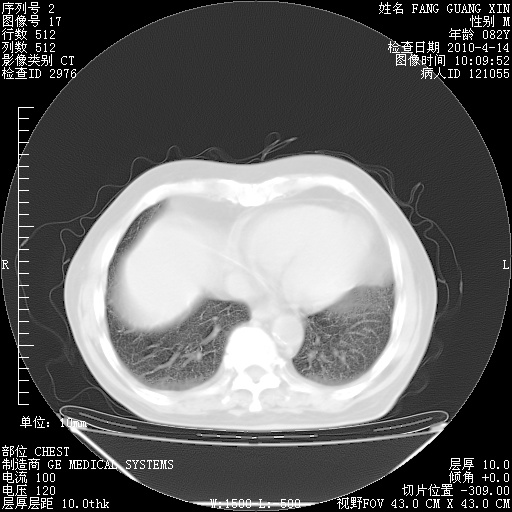

肺部CT平扫未见异常。